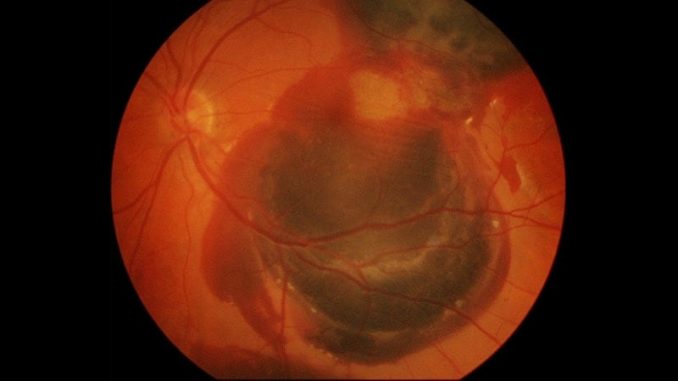

A gene therapy that aims to increase levels of two key proteins that enable the growth of new blood vessels in age-related macular degeneration (AMD) was shown to stabilize vision with a low rate of ocular side effects while reducing the need for intraocular injections by 81% through 9 months, researchers have found.

The PRISM trial evaluated three doses of the therapy, 4d-150, and found that the two highest doses — 1 x 1010 (1e10) and 3 x 1010 (3e10) vector genes (vg)/eye — were most effective at maintaining best-corrected visual acuity (BCVA) and restoring retinal central subfield thickness (CST) through 36 weeks, said Christine Kay, MD, director of retinal genetics at Vitreoretinal Associates in Gainesville, Florida, who helped conduct the study. The phase 1/2 trial enrolled five patients in each dosing cohort for a total of 15 patients.

4D-150 is a dual transgene therapy designed to activate production of the proteins aflibercept and vascular endothelial growth factor-C (VEGF-C) RNAi, both of which maintain retinal vascular integrity and inhibit new vessel formation in neovascular AMD. The treatment is injected directly into the vitreous of the eye in the office and does not require ocular surgery to place a gene vector below the retina, which is the delivery vehicle for other investigative gene therapies for retinal disease.

“BCVA was stable,” Kay said. “The 3.6-letter reduction in the high-dose group was irrelevant, but CST [central subfield thickness] did show a dosing response.” The 3e10 group experienced a 92 (± 49) µm reduction in CST, a key anatomical biomarker of retinal integrity, from baseline, Kay said. “There is a dose-response here,” she said.